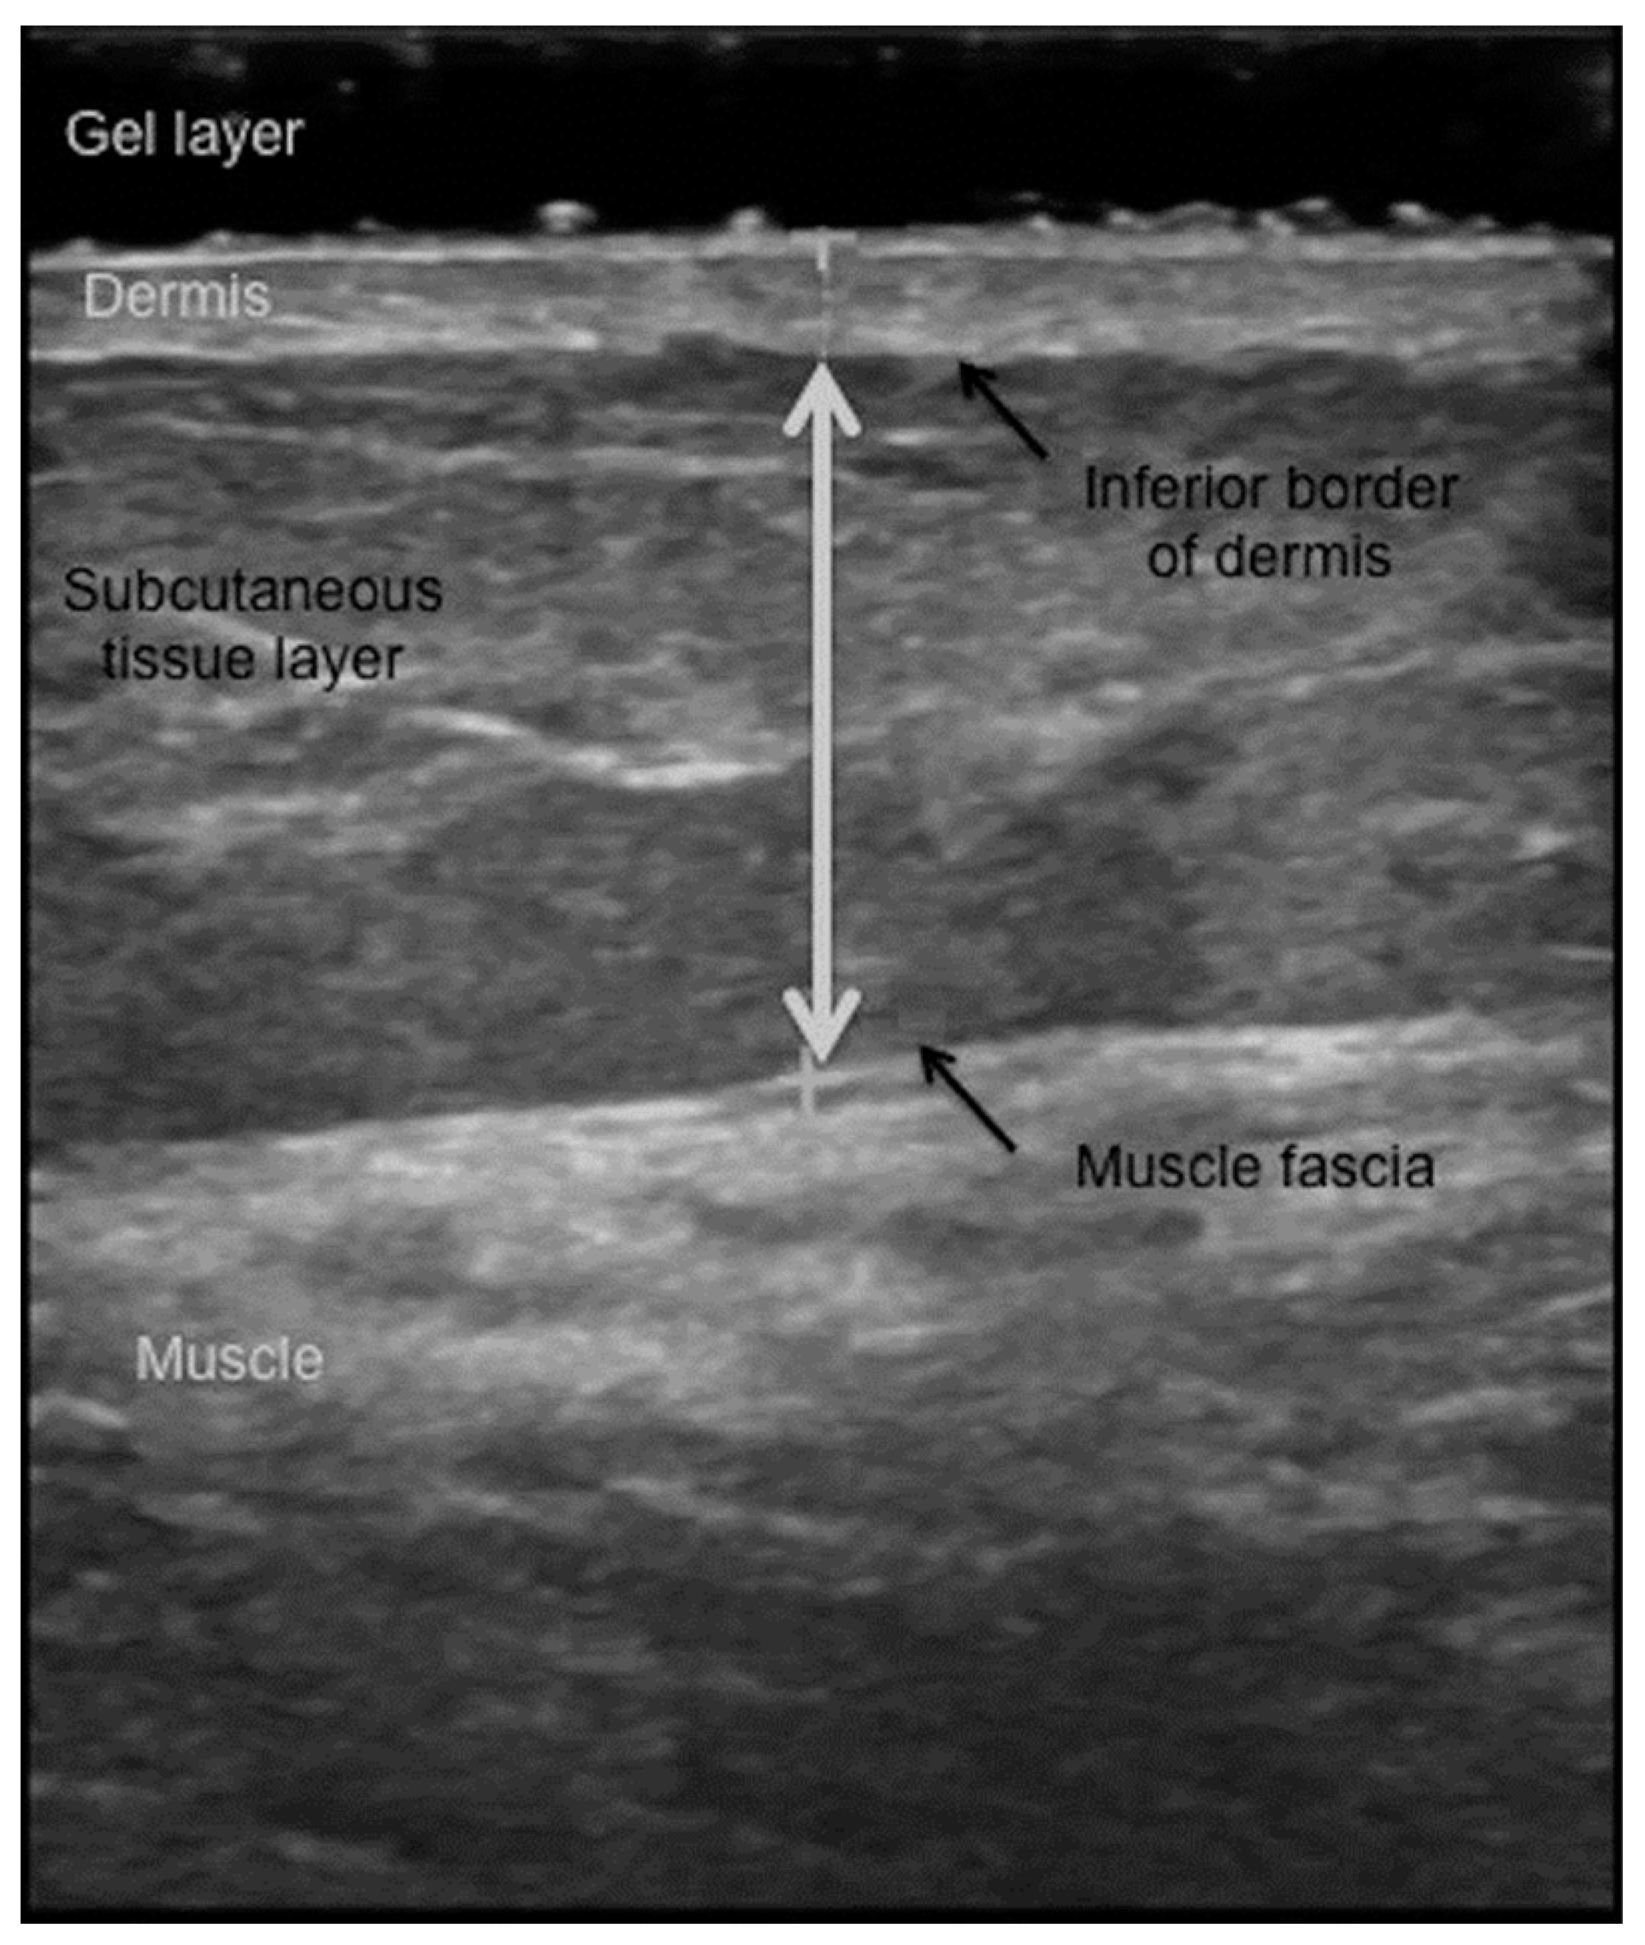

- Toomey, C.; McCreesh, K.; Leahy, S.; Jakeman, P. Technical considerations for accurate measurement of subcutaneous adipose tissue thickness using B-mode ultrasound. Ultrasound 2011, 19, 91–96. [Google Scholar] [CrossRef]